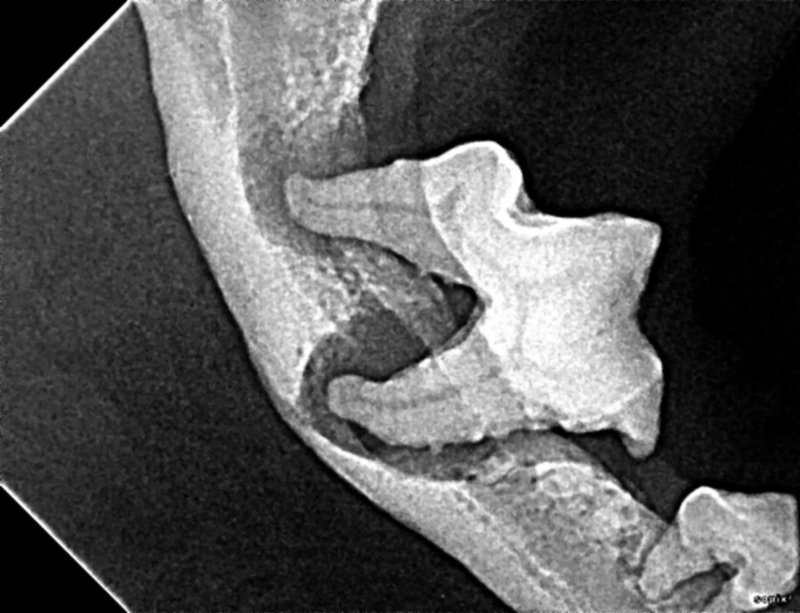

Pets can be involved in trauma that can cause fractures to their head, teeth, and jaw bones. Correctly repairing these fractures is extremely important for your pet to have normal function of their mouth. If a jaw fracture is allowed to heal in an abnormal position, your pet may have great difficulty chewing and can be in significant pain. Many fractures can be successfully treated with minimally invasive oral procedures, but more complicated cases may require bone plating techniques. The Center offers cone beam CT imaging which provides extremely detailed images of the bones of the head and skull. Advanced imaging with CBCT facilitates selection of the best surgical technique to get your pet back to eating and comfort as soon as possible.

The Center now provides advanced imaging via cone beam CT. Cone beam CT is excellent for visualization of bony structures of the skull, nasal cavity, teeth, and ears. Cone beam CT is especially helpful for diagnosing dental disease and evaluation of jaw fractures. It can also be useful for evaluating the sinuses and tympanic bulla. Cone beam CT can be used in conjunction with nasal biopsy and culture to evaluate nasal discharge whether chronic or acute.